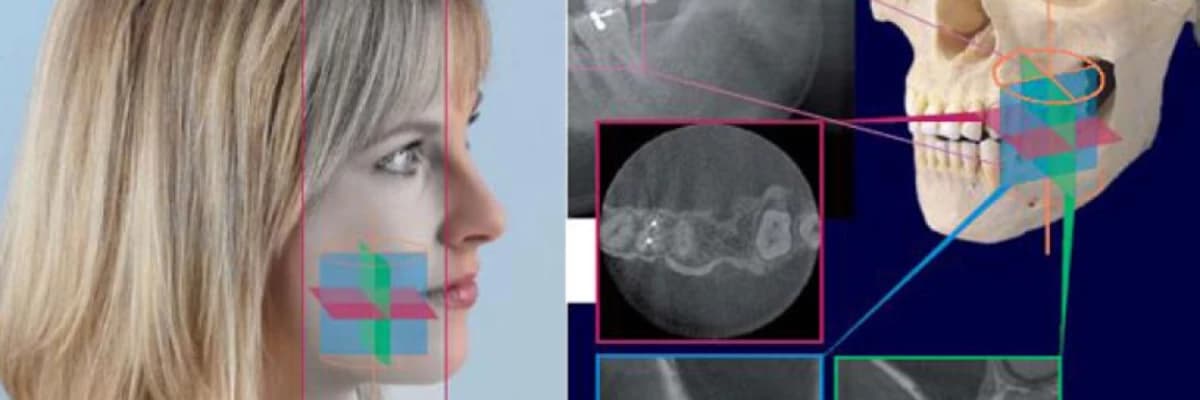

Dental 3D Tomografi çekimi nasıl yapılır?

•Önce iki yönlü dijital rehber görüntü çekilir.

•Hasta cihazdan çıkmadan ekrandaki görüntü üzerinde hedef bölge belirlenir.

•Hedeflenen bölgeden 3 boyutlu bir alanın djital hacimsel tomografik (DVT) görüntüsü alınır.

Hacimsel 3D görüntüden nasıl faydalanabilirsiniz?

•Panoramik ve periapikal röntgen ile pozlanamayan alanları görüntüleyebilirsiniz.

•Çekilen görüntüden koronal, aksiyal, sagital (cross section) kesitler alıp daha detaylı teşhis yapabilirsiniz.

•Implant planlama ve cerrahi klavuz hazırlama için yüksek çözünürlüklü data elde edebilirsiniz.

•Volume rendering: 3 Boyutlu kafatası yapısı ve kemikler görüntülenebilir.